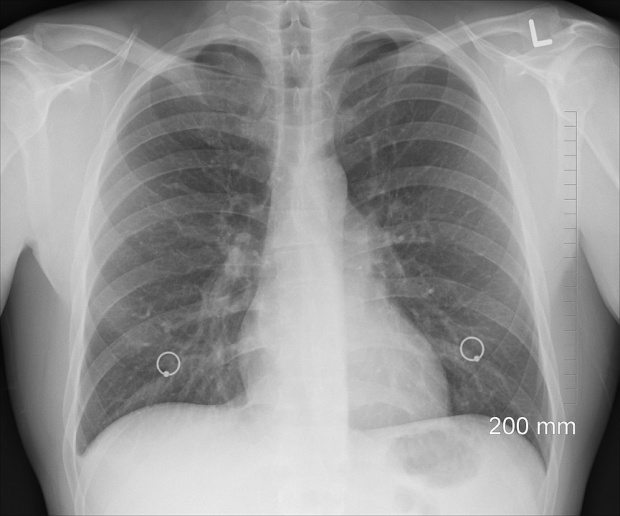

BPOC (bronhopneumopatie obstructiva cronica) este o boala de plamani care cauzeaza anual moartea a trei milioane de oameni la nivel mondial, si aproape jumatate dintre pacienti nu stiu ca au boala.

in Romania, aproximativ un milion de oameni sufera de BPOC, scrie doctorulzilei.ro.

Simptomele timpurii ale bolii nu sunt recunoscute, mai ales din cauza faptului ca tusea, senzatia de sufocare, oboseala par a fi consecinte firesti ale fumatului sau inaintarii in virsta.